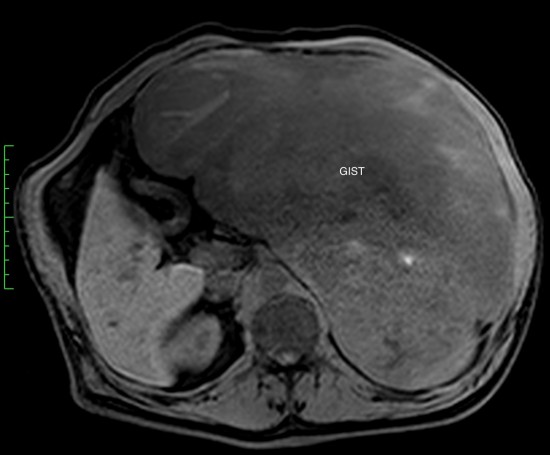

Гастроинтестинальная стромальная опухоль гигантских размеров, исходящая из большой кривизны желудка